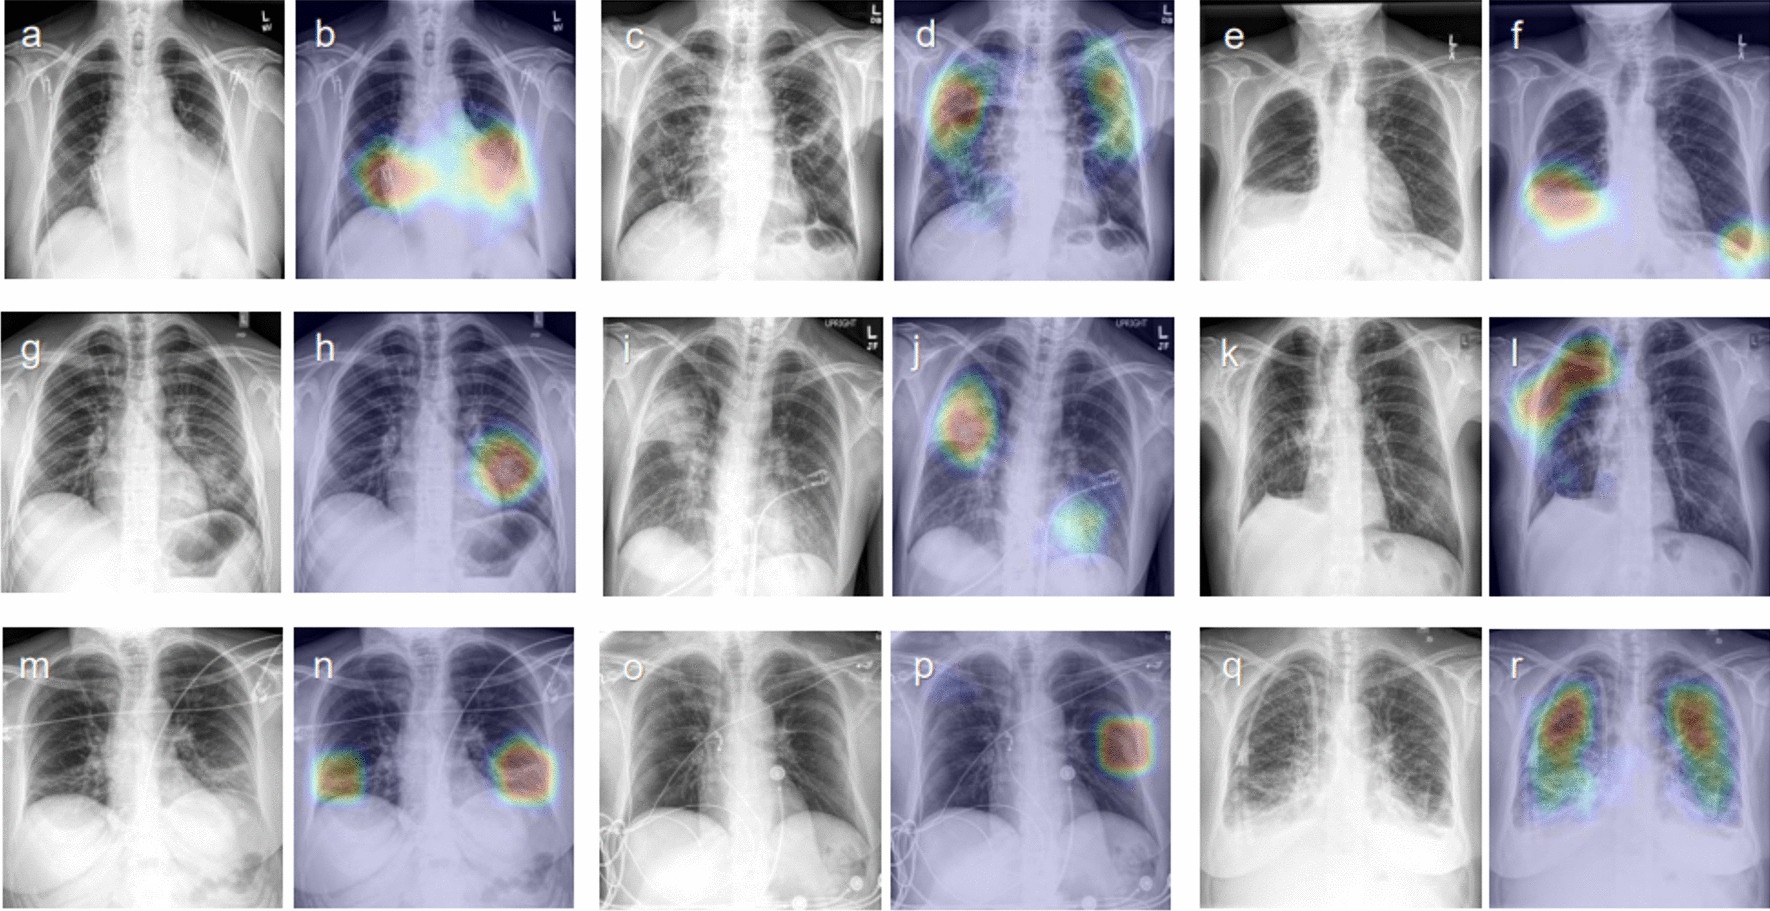

Figure 1

Representative class activation maps (CAMs) with correct lesion localization. (a,b) Cardiomegaly (PA), (c,d) Other interstitial opacity (PA), (e,f) Pleural effusion (PA), (g,h) Pneumonia (PA), (i,j) Pneumonia (AP), (k,l) Pneumothorax (PA), (m,n) Atelectasis (AP), (o,p) Fracture (AP), (q,r) Pulmonary edema (PA).